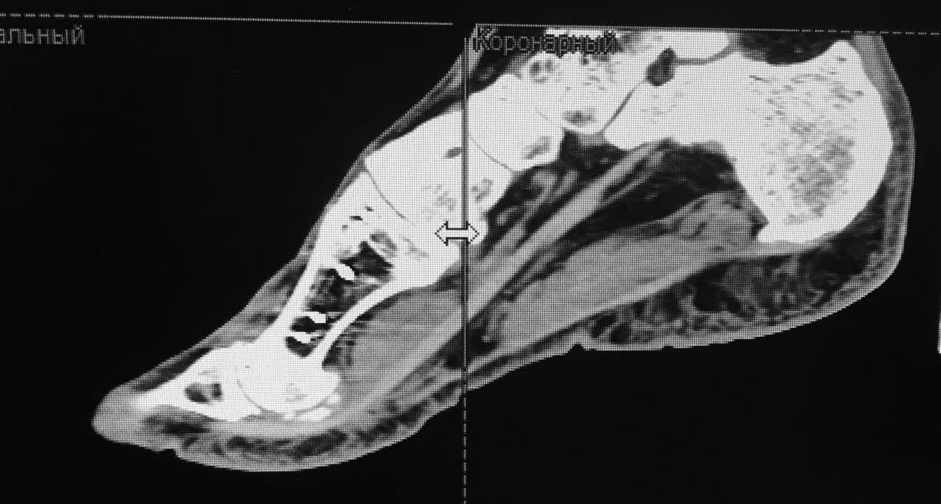

женщина средних лет, оперирована около года назад

Насколько я понял, беспокоит метатарсалгия. Достаточно будет укоротить

II-IV? Что-то другое? на что обратить внимание?